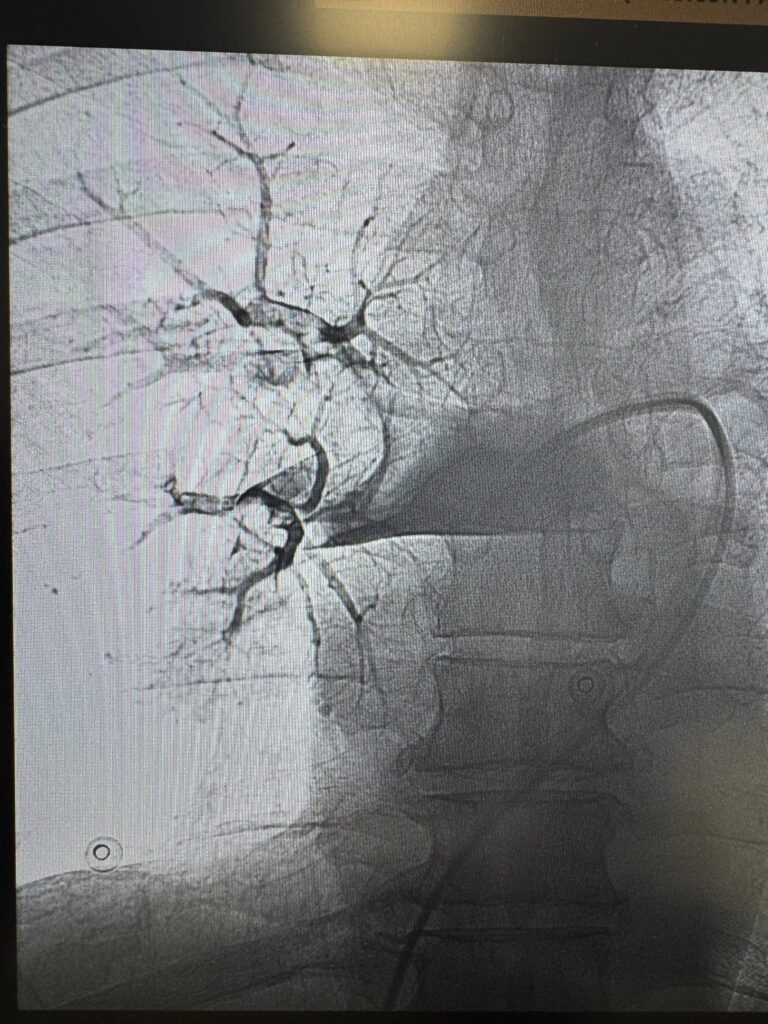

Команда лікарів Першого територіального медичного об’єднання міста Львова прийняла рішення в обох випадках провести ендоваскулярну тромбаспірацію — сучасне, малоінвазивне втручання, що дозволяє механічно видалити тромб із легеневої артерії без відкритої операції. Саме цю методику освоїли нещодавно на конгресі інтервенційних радіологів в Барселоні!

Під рентгенконтролем через судини катетером ми дісталися тромбів й видалили їх спеціальною системою аспірації.

Пацієнти уже через кілька годин з позитивною динамікою, стабілізувались гемодинамічно, і живі — завдяки швидкому рішенню, професійності команди та сучасним технологіям.